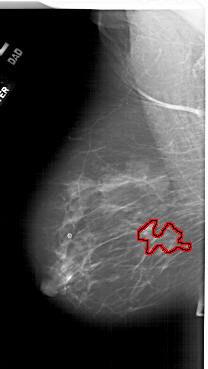

A_1788_1.LEFT_MLO

LEFT_MLO LINES 6271 PIXELS_PER_LINE 3526 BITS_PER_PIXEL 12 RESOLUTION 43.5 OVERLAY

FILE: A_1788_1.LEFT_MLO.OVERLAY

TOTAL_ABNORMALITIES 1

ABNORMALITY 1

LESION_TYPE MASS SHAPE IRREGULAR MARGINS SPICULATED

ASSESSMENT 4

SUBTLETY 4

PATHOLOGY BENIGN

TOTAL_OUTLINES 1

BOUNDARY